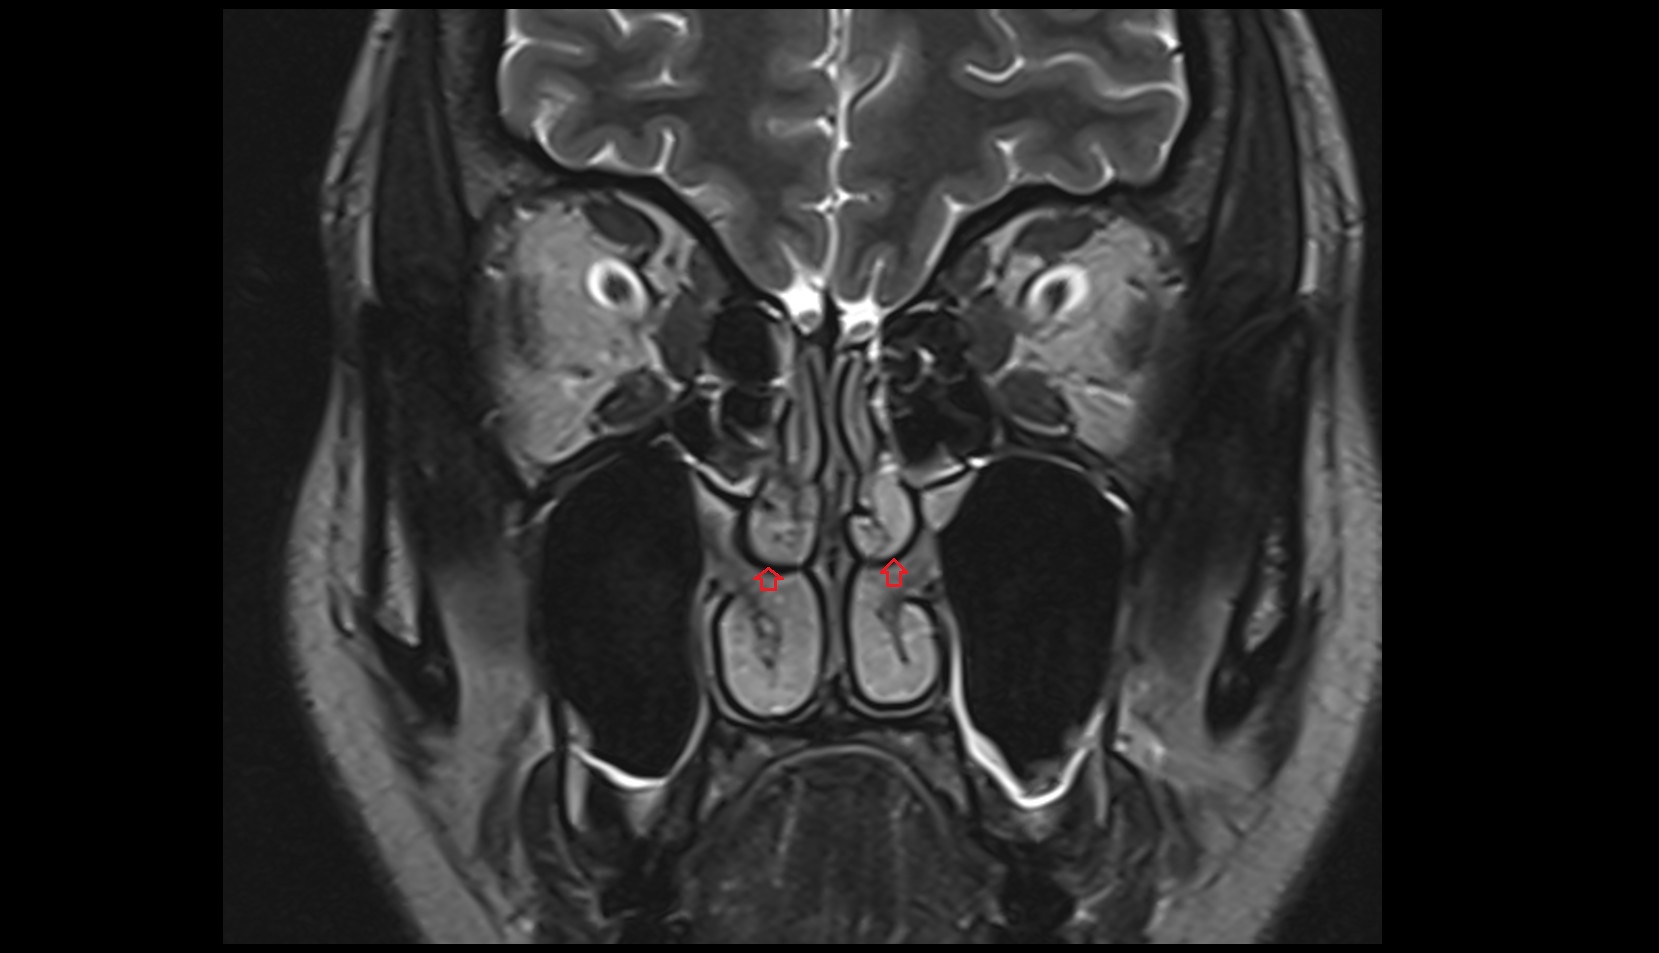

- Hippocampus

- Body of hippocampus

- Head of hippocampus

- Tail of hippocampus